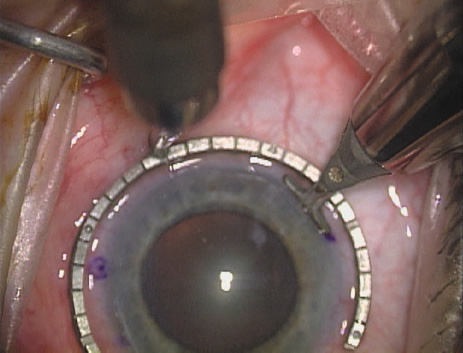

Case 2 is a 79-year-old woman who presented with a very dense left cataract. Her refraction was recorded at −2.25 +2.75 × 125 with a difficult end point. Her manual keratometry and topography measurements were consistent and revealed slightly less than 1.75 D at 120 degrees. Because of the questionable refraction, greater value was placed on the corneal measurements. Based upon the cataract nomogram, the plan was for paired LRIs of 40 degrees to be placed over the steep 120-degree axis (Figs. 1219).

Fig. 16. The starting point of the opposing incision is determined. (Reprinted from Hardten DR, Lindstrom RL, Davis EA. Phakic Intraocular Lenses: Principles and Practice. Thorofare, NJ: SLACK Incorporated, 2004, with permission.)

Fig. 17. The opposing incision is begun. (Reprinted from Hardten DR, Lindstrom RL, Davis EA. Phakic Intraocular Lenses: Principles and Practice. Thorofare, NJ: SLACK Incorporated, 2004, with permission.)

Fig. 18. The incision is completed. (Reprinted from Hardten DR, Lindstrom RL, Davis EA. Phakic Intraocular Lenses: Principles and Practice. Thorofare, NJ: SLACK Incorporated, 2004, with permission.)

Fig. 19. The temporal single-plane clear corneal incision is placed independent of the LRIs. (Reprinted from Hardten DR, Lindstrom RL, Davis EA. Phakic Intraocular Lenses: Principles and Practice. Thorofare, NJ: SLACK Incorporated, 2004, with permission.)